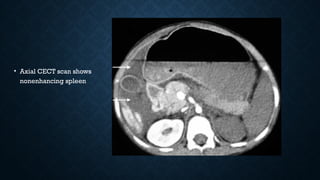

• Axial CECT scan shows

nonenhancing spleen

• Axial CECTscan shows nonenhancing spleen